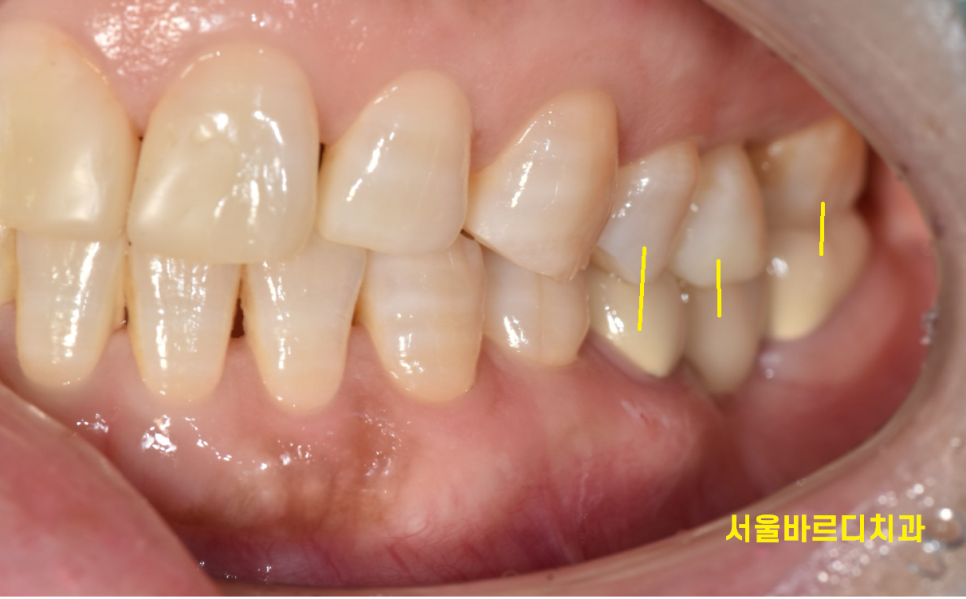

교합(씹는 부분)은 잘 맞는데

교합이 잘 안맞는데 앞니만 교정할 수는 없어요.

심한 부정교합의 경우에는

치아를 전반적으로 움직여주어야하지만

아래 치아가 없는 부분은 임플란트 치료중이신데

앞니만 교정하기 때문에 임플란트 치료중에도 받으실 수 있습니다!